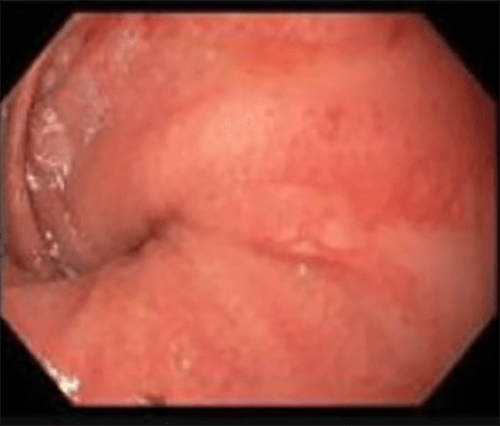

This patient is a 40-year-old female with a history of refractory ulcerative colitis (UC) who is status post 3-stage total proctocolectomy (TP) with ileal pouch-anal anastomosis (IPAA). She underwent reversal of the loop ileostomy in March 2016. In July 2017, she presented to the emergency room with obstipation, nausea, and vomiting. Workup, including pouchoscopy, was suspicious for a pouch volvulus (Figure 1). She was subsequently taken to the operating room and underwent a laparoscopic detorsion of the J pouch with pouch pexy. Multiple interrupted non-absorbable braided polyester sutures were placed tacking the left lateral aspect of the pouch to the pelvic sidewall/peritoneum. During this procedure the patient was noted to have a free-floating pouch without any adhesions between the pouch and the sacral hollow. The patient recovered uneventfully and had good return of bowel function post-operatively.

Figure 1. Endoscopic view showing pinwheeling of pouch torsion (2017)